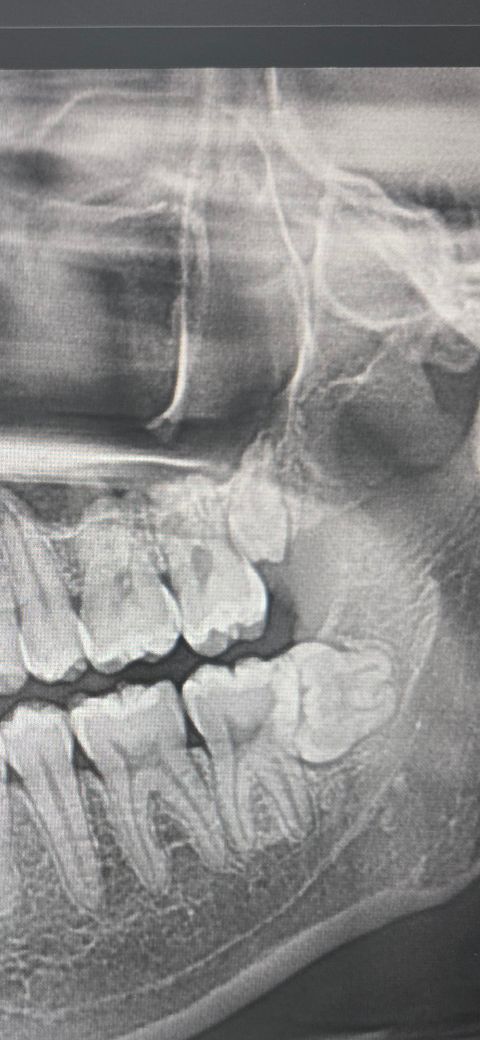

위쪽 사랑니 어떻게 생긴 사랑니인지 알수있나요?

위에 있는 사랑니가 일반적인 사랑니랑 다르게 생겼는데 자라다 만 사랑니인가요? 아님 방향이 돌아가있는건가요?

씹는면이 약간 정면 보고 있는거같기도 하고?

위의 사랑니가 잇몸에 묻혀 있는 상태 즉 매복사랑니 입니다. 사랑니 사이즈가 조금 작습니다. 위의 사랑니는 사이즈가 작은 경우가 종종 있습니다.

사랑니가 왜소치라고 생각하시면됩니다. 그냥 다른 치아에 비해서 작은거죠. 잇몸에 살짝 뭍혀 잇는 상태 같습니다.

왼쪽 위의 사랑니가 왜소치 형태로 작게 발생이 된 것으로 보입니다. 맹출되지 않았다면 크게 문제가 되지 않기 때문에 그냥 사용해도 됩니다.

위에 있는 사랑니가 일반적인 사랑니랑 다르게 생겼는데 자라다 만 사랑니인가요? 아님 방향이 돌아가있는건가요?사랑니는 원래 형태가 다양합니다.

각도는 정상인데 왜소한 사랑니입니다 원래 사랑니는 형태상 변이가 많습니다 불편하면 발치하시면 됩니다